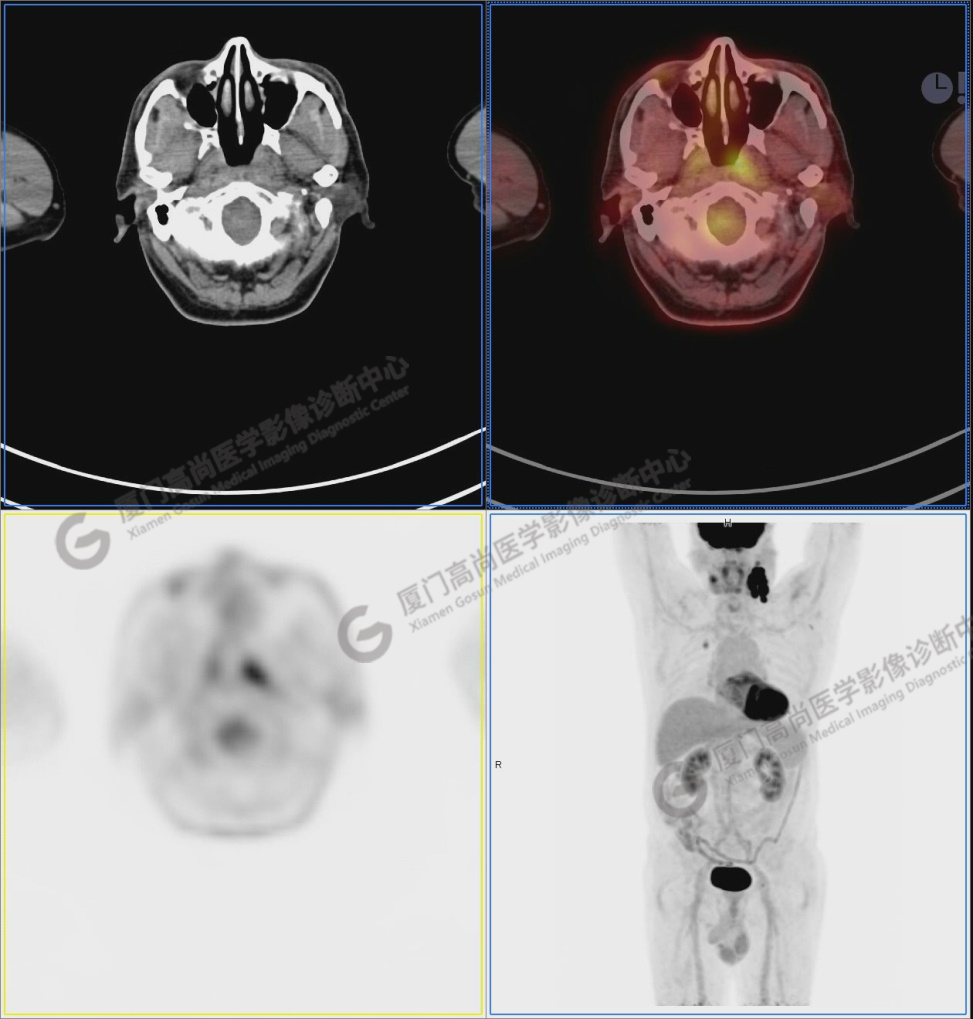

PET/CT影像圖

圖1:PET/CT全身圖像

圖2:雙側(cè)頸部多發(fā)增大淋巴結(jié),代謝不同程度增高,考慮為轉(zhuǎn)移。

圖6-9:鼻咽左側(cè)壁增厚,代謝異常增高,考慮為鼻咽癌